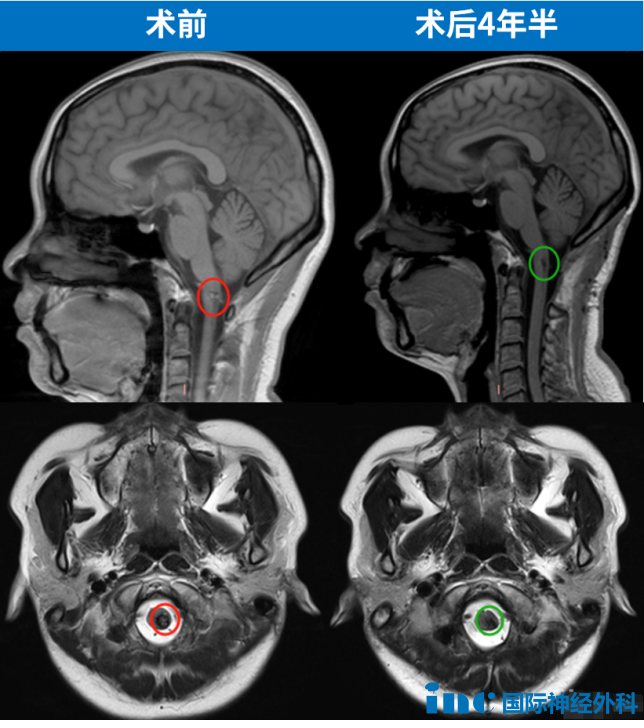

2021年,在经过四年的保守治疗与症状反复后,患者最终接受开颅手术治疗脑干-延髓海绵状血管瘤。这一关键治疗决策耗时四年才得以实施。在此期间,医生的保守建议与持续进展的病情形成拉锯,反复出血导致症状加剧。“当手术真正来临时,我突然意识到这个决定做得有些晚了,如果手术后状态差一些我也能接受。”患者坦言。

公司领导批准病假支持治疗,母亲陪同至手术医院提供术后照顾。ICU期间巴教授探视鼓励,术后第二天转出ICU与母亲团聚。术后五天可下床活动,与教授合影留念。术后十二天出院,MRI显示病变完全切除,多年脑血管疾病终获解决。